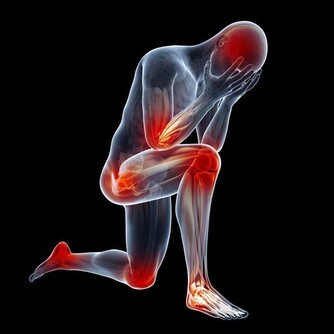

腸胃寒涼一般是中醫的說法。如今患有胃病的人是越來越多了,都是因為現代人的飲食習慣不好、作息不規律所導致的。其中,胃寒常見的腸胃功能不良的現象。胃寒雖然不是指具體的病症,卻能夠引發許多不好的併發症。因此,一定要注意日常的調理。那麼,腸胃寒這種情況該怎麼調理呢?

針灸物理治療

1.公孫穴(在腳內側,也就是大腳趾關節後邊有一個突出的骨頭,就在這個骨頭後的凹陷處)

公孫穴是人體的八脈交會穴之一的“沖脈之會” 沖脈為經脈之海,其特徵是“主滲灌溪谷”;同時也是脾經的“絡穴”,是十分重要的穴位。 「公孫者,輩分也。」脾經屬土,其父為火,其公為木,其子為金,其孫為水。意思是指本穴為脾經與沖脈的氣血相會後化成了水濕風氣,有聯絡脾胃二經各部氣血的作用。此穴能調動脾經的運作能力,不僅能抑制胃酸和促進小腸蠕動,還能治療婦科病,有通氣和活血化瘀之效。

2.地機穴(「陰陵泉」下四橫指處:在腿肚子上的最高點貼著脛骨的地方)

「地者,土也;機者,生機也。」意指人體營養的重要來源之地。脾屬土,是人體後天運化之本,這個在前面《衛氣與營氣》的文章中已經介紹過了,點揉此穴能增強整個腸胃的運化功能,如果配合「三陰交」穴還能治療經痛;配合「隱白穴」能治療崩漏等婦科疾病。

3. 內關穴(掌心向上,腕橫紋上2寸:兩個半橫指處)

內關穴屬於心包經,是治療心胸胃疼痛的重要穴位。 「內者,內部也;。關者,關卡也。」顧名思義就是此穴就像一道血液的閘門有疏導水濕的作用。像是打嗝、胃痛、偏頭痛、噁心、嘔吐、血壓高低的調節都是它的拿手好戲,但是體虛之人揉內關的效果不明顯,因為「內關穴」只有在氣血旺而遭到阻塞時才能發揮作用(開閘放水),它是衝鋒的穴位,不是個補穴。文章來源: /c/user/token/MS4wLjABAAAAARSimWY-YeSR6zdChv7Q3b5LxayKCC4NraQXzHRQGaE/?source=tuwen_detail